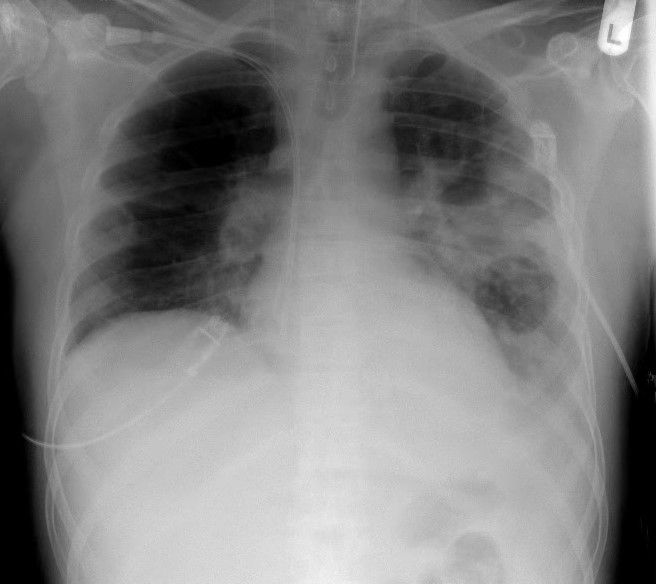

อาการที่ตามมาจึงแสดงออกผ่านอวัยวะที่มีเมือกอุดตัน หากเกิดที่ปอด เมือกข้นเหนียวจะเข้าไปอุดตันหลอดลมฝอย ทำให้ขนขนาดเล็กในปอดไม่สามารถโบกพัดสิ่งสกปรกออกมาได้ กลายเป็นแหล่งสะสมของแบคทีเรียชั้นดี นำไปสู่การติดเชื้อในปอดซ้ำซาก ไอเรื้อรัง และปอดอักเสบจนเนื้อเยื่อปอดถูกทำลาย ในขณะเดียวกันที่ระบบย่อยอาหาร เมือกเหนียวจะไปอุดตันท่อตับอ่อน ขัดขวางไม่ให้น้ำย่อยเดินทางไปย่อยอาหารที่ลำไส้เล็ก ผู้ป่วยจึงมักมีปัญหาการดูดซึมสารอาหาร ถ่ายอุจจาระเป็นมัน ร่างกายผอมแห้งแม้กินอาหารมาก และขาดวิตามิน นอกจากนี้ยังมีอาการที่เป็นเอกลักษณ์คือ ผิวหนังมีรสเค็มจัด เนื่องจากความผิดปกติของช่องทางเกลือที่ต่อมเหงื่อทำให้ร่างกายสูญเสียเกลือออกมาทางผิวหนังมากกว่าคนปกติ

อย่างไรก็ตาม ความหวังของผู้ป่วยในยุคปัจจุบันดีกว่าในอดีตมาก ด้วยพัฒนาการทางการแพทย์ที่มีการคิดค้นยากลุ่มใหม่ที่เรียกว่า Modulators ซึ่งสามารถเข้าไปแก้ไขความผิดปกติที่ตัวโปรตีน CFTR ได้โดยตรง ทำให้กลไกการแลกเปลี่ยนเกลือและน้ำกลับมาทำงานได้ดีขึ้น แม้ยาจะมีราคาแพงมหาศาล แต่ก็ช่วยเปลี่ยนจากโรคที่เคยพรากชีวิตเด็กตั้งแต่วัยทารก ให้กลายเป็นโรคเรื้อรังที่ผู้ป่วยสามารถเติบโต เรียนหนังสือ และมีชีวิตอยู่จนถึงวัยผู้ใหญ่ได้ แต่หากอาการทรุดหนักจนปอดเสียหายถาวร การปลูกถ่ายปอดจะเป็นทางเลือกสุดท้ายในการต่อลมหายใจ แม้จะไม่ใช่การรักษาที่ต้นเหตุของพันธุกรรมก็ตาม